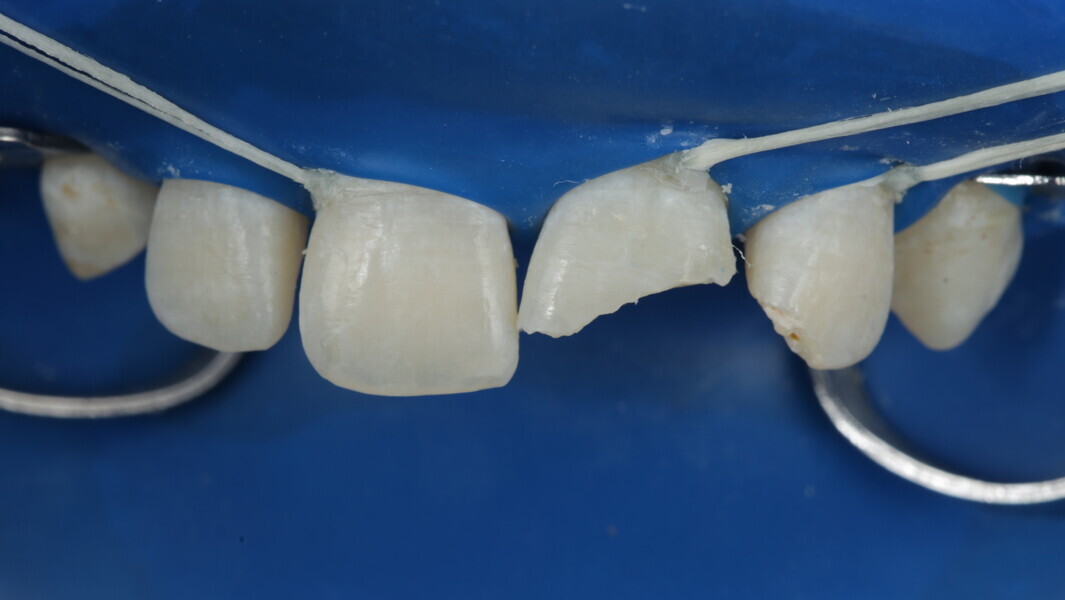

A 10-year-old male patient reported with a complaint of trauma to the upper left central and lateral incisors, involving the enamel and dentin. Direct composite was used in multi-layers and the smile was restored. This article explains detailed steps in the polychromatic layering technique with special emphasis on the finishing and polishing protocol. 3M Espe Filtex Z350 Xt was used with a universal bonding agent.

Fig 19-24: Contact build-up with band and wedge

Fig 25-30: Layering protocol step by step